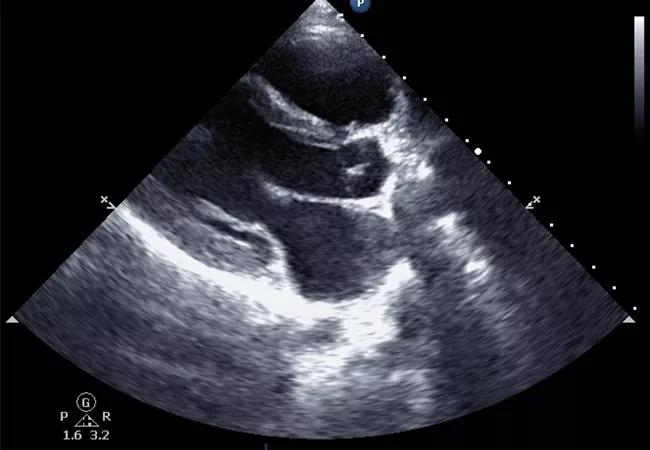

The final challenge in evaluating patients with suspected PAH is to estimate their risk of death. Although nonmodifiable risk factors including age, sex and associated comorbidities play a significant role in determining prognosis, several potentially modifiable risk factors should be used to estimate the one-year mortality risk. These include features on physical examination consistent with right heart failure, New York Heart Association functional class, six-minute walking distance or cardiopulmonary exercise capacity, N-terminal pro-B-type natriuretic peptide (NT-proBNP) level and findings on echocardiography and right heart catheterization.

Cardiac magnetic resonance imaging (MRI) has gained popularity as a noninvasive and reproducible alternative to echocardiography. Image fidelity and characterization of right ventricular function and right ventricular ejection fraction are all more accurate than with echocardiography, and serial MRI has proven valuable in its ability to guide patient prognosis.

However, MRI is more expensive than echocardiography, and some patients cannot tolerate the procedure. In addition, for those who can tolerate it, MRI is not a suitable alternative to right heart catheterization, since it cannot accurately estimate pulmonary artery occlusion pressure or pulmonary arterial pressures. For these reasons, cardiac MRI use varies across pulmonary hypertension centers.